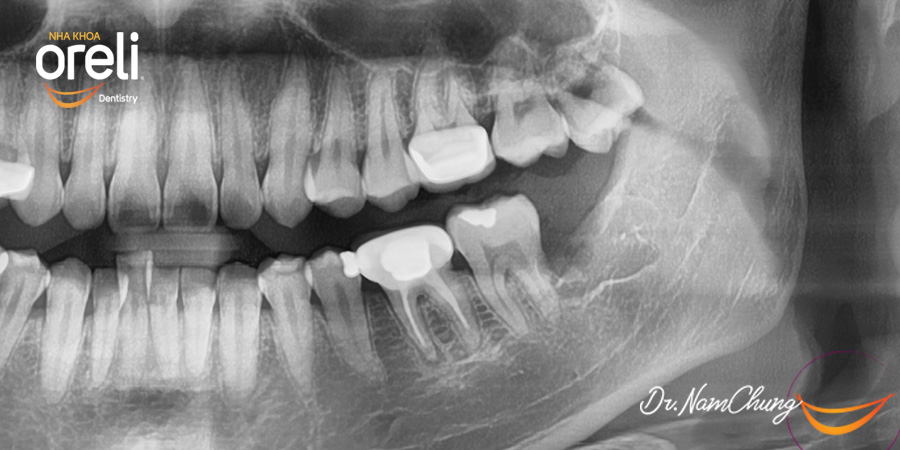

Nhổ răng khôn hàm dưới mọc lệch – Ca thực tế tại Oreli Buôn Ma Thuột

Nhổ răng khôn

Mọc lệch